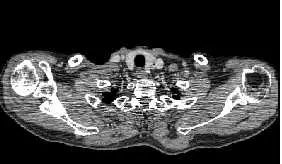

本題影像為骨盆區域 CT 橫斷面,可見:

- 雙側人工髖關節(bilateral hip prostheses):左右兩側均可見高密度金屬植入物(白色致密影),為典型金屬植入物外觀

- 嚴重黑色條帶與暗紋:在兩側金屬植入物之間的中央區域(骨盆中線附近),出現大範圍深黑色條帶,解剖結構完全無法辨認

- 輻射狀條帶延伸:暗條帶沿最高衰減方向(從一側金屬植入物穿越中線至另一側)呈放射狀分布

- 兩側金屬植入物周圍亦有亮暗交替條紋:金屬邊緣附近可見星芒狀亮暗相間條帶,為光子飢渴與射束硬化(beam hardening)的複合表現

- 假影嚴重程度與雙側金屬有關:相較單側植入物,雙側人工髖關節使 X 光束必須穿越兩個高衰減結構,光子飢渴效應倍增,假影更為嚴重

此影像特徵最符合**光子飢渴假影(photon sta